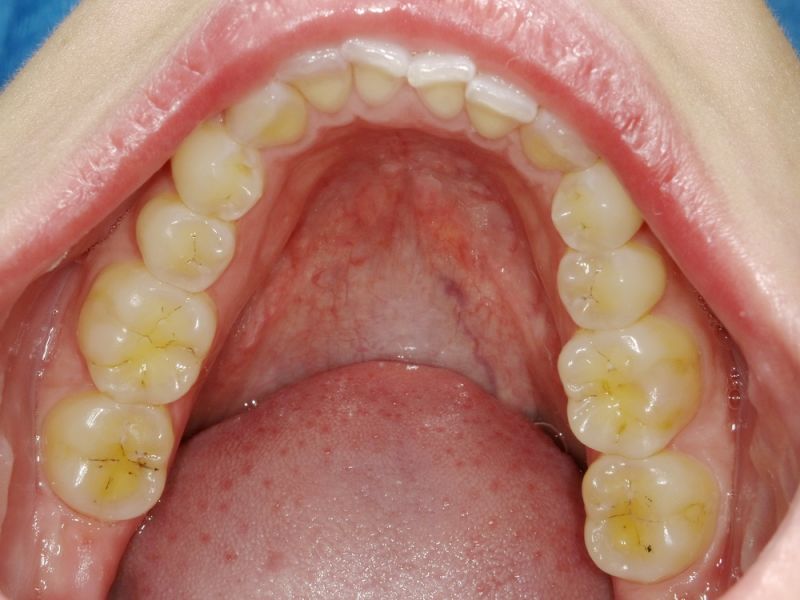

Ganz aktuell war die Patientin bei einer Hauszahnärztin, die auf die Idee kam der Patientin zwei Eckzahnfacetten im Oberkiefer zu installieren, mit dem Ergebnis, dass die Beschwerden der Patienti sich nochmals verschlechtert haben.

Auch hier einmal wieder mehr: Eine kurzentschlossene Therapie, ohne jede vorhergehende Diagnostik. Im zahnärztlichen Bereich eher üblich, als außergewöhnlich. Wir denken nur an die üblichen Geschichten vermeintlicher Erosionen, bei denn die Patienten am Tag 370 Liter Cola und 580 Yoghurts essen müssten, um die ph Werte zu realisieren, die für erosive Zahnsubstanzverluste Voraussetzung wären.

Das in Wirklichkeit unphysiologische okklusale Belastungen, hervorgerufen durch latente funktionelle Fehlbelastungen der Zahnoberflächen die Ursache von Vorschädigungen der Zahnhartsubstanzen sind, so dass dann tatsächlich schon das normale Zähneputzen zu Zahnsubstanzverlusten führen kann, geht dabei unter.